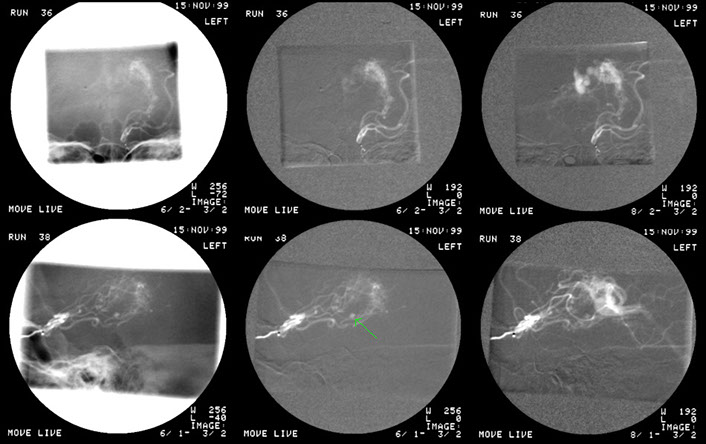

This patient was disturbed in his sleep by a noise in the head. Injection of the left common carotid artery revealed abnormal circulation over the posterior aspect of the brain which was shown to be supplied by a branch of the occipital artery which drained via small vessels into a larger vein.

The flow was gradually occluded by embolisation with particulate material until flow ceased. It is recommended that the venous end is also occluded to prevent recurrence of flow through the fistula via collaterals. This was not done at the initial session and the patient did return with recurrent symptoms two years later.